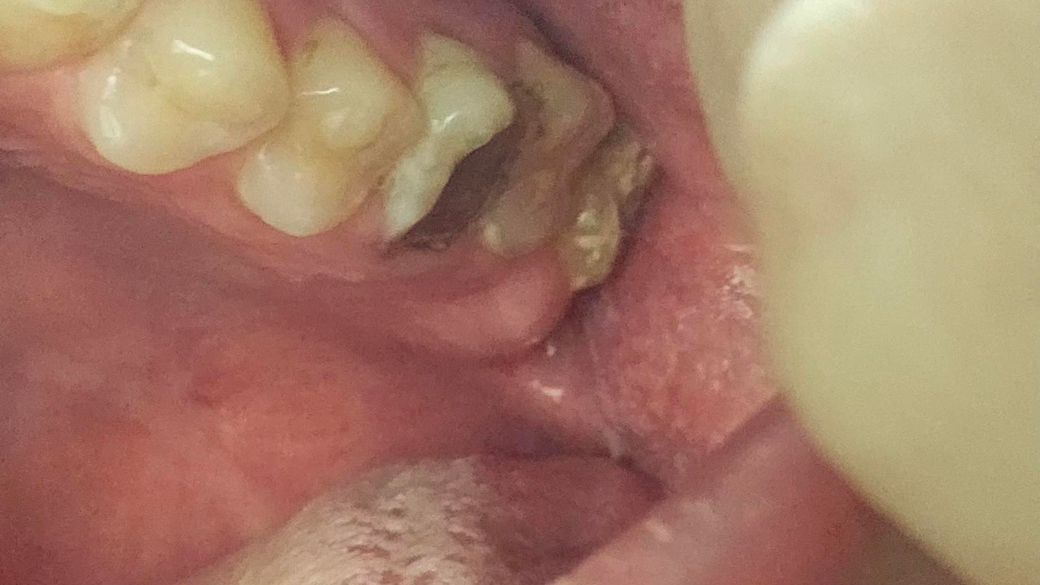

이사진 에있는이빨들은 치과에서 뽑아하는상태인가요?

아니면 발치할가능성은많이없나요

나머지 이빨상태 괜찮은것가요

신경치료 또는 충치치료 할가능성 많이있나요

정확한건 엑스레이를 찍어봐야 알겟지만 저정도 상태라면 발치를 해야될 가능성이 높아 보입니다.

사진으로 봤을 경우에는 충치가 이미 많이 진행된 것으로 보입니다. 충치가 진행되어 치아에 뿌리까지 충치가 진행되었다면 치아를 발치해야 할 수 있습니다.

자세한 확인을 위해서 치과에서 진료를 받아보는 것을 권유드립니다.

1,3번째 사진의 치아는 신경치료 시도해보나 빼야할 가능성이 높습니다

2번째 치아는 이소맹출 치아이고 불완전한 상태이므로 뺍니다

마취합니다